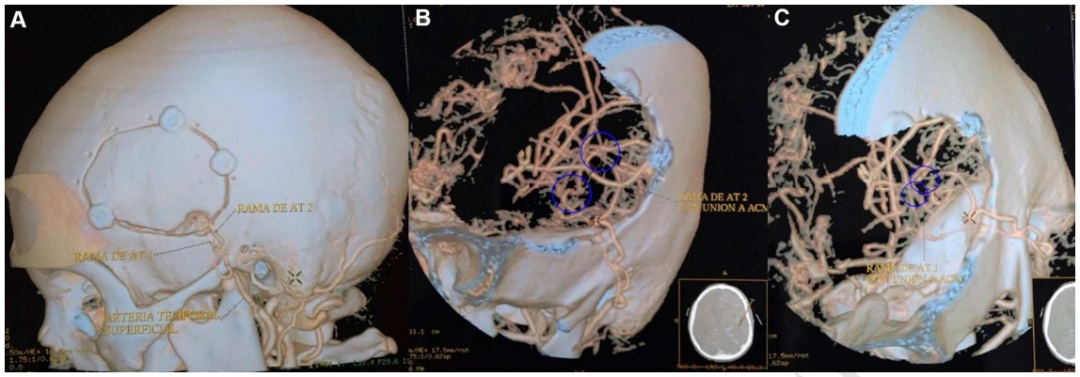

因此,该患者在左颞浅动脉和左大脑中动脉之间接受了两次直接搭桥手术,由主刀川岛明次教授完成手术(图2)。

▼图2术后CTA的3D重建显示开颅手术大小,以及在左侧颞浅动脉和左侧大脑中动脉之间进行的两次搭桥血管重建。